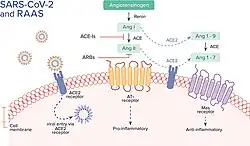

The SARS-CoV-2 virus can infect a wide range of cells and systems of the body. COVID‑19 is most known for affecting the upper respiratory tract (sinuses, nose, and throat) and the lower respiratory tract (windpipe and lungs).[125] The lungs are the organs most affected by COVID‑19 because the virus accesses host cells via the receptor for the enzyme angiotensin-converting enzyme 2 (ACE2), which is most abundant on the surface of type II alveolar cells of the lungs.[126] The virus uses a special surface glycoprotein called a "spike" to connect to the ACE2 receptor and enter the host cell.[127]

Human angiotensin converting enzyme 2 (hACE2) is the host factor that SARS-CoV-2 virus targets causing COVID‑19. Theoretically, the usage of angiotensin receptor blockers (ARB) and ACE inhibitors upregulating ACE2 expression might increase morbidity with COVID‑19, though animal data suggest some potential protective effect of ARB; however no clinical studies have proven susceptibility or outcomes. Until further data is available, guidelines and recommendations for people with hypertension remain.[164]

The effect of the virus on ACE2 cell surfaces leads to leukocytic infiltration, increased blood vessel permeability, alveolar wall permeability, as well as decreased secretion of lung surfactants. These effects cause the majority of the respiratory symptoms. However, the aggravation of local inflammation causes a cytokine storm eventually leading to a systemic inflammatory response syndrome.[165]